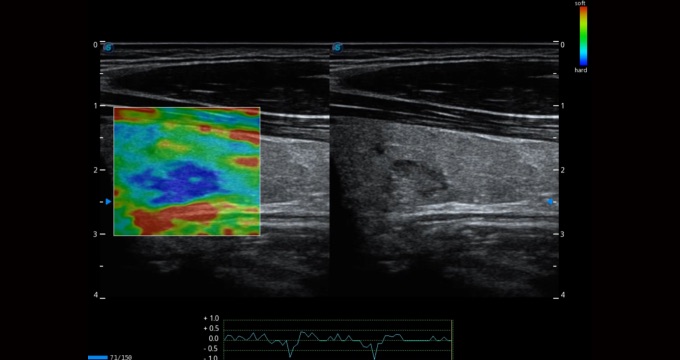

Single crystal transducers greatly improve signal ratio, acquire stunning images and provide superior sensitivity and resolution for both the near and far fields, by increasing the uniformity of crystal alignment and raising energy transmission efficiency. Single crystal C1-5 for abdominal and OB patients and S1-5 for cardiology and transcranial applications. Composite crystal linear transducers, by reforming the conventional piezoelectric materials, achieve a better acoustic spectrum and lower acoustic impedance to serve well in vascular, breast, thyroid, MSK, etc. The combo of 12L-A, 12L-B, 9L-A covers an ultra-wide frequency bandwidth, leaving nearly no blind spot for all sorts of scanning.